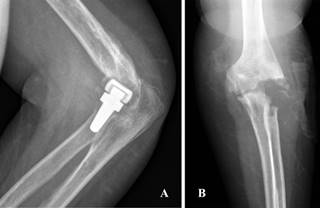

En lo que respecta a complicaciones relativas a la intervención, un total de 13 pacientes (27%) las presentaron. Se diagnosticaron tres casos de infección de la herida quirúrgica, dos de los cuales fueron superficiales y se resolvieron satisfactoriamente con antibioterapia. El caso restante corresponde a una infección profunda quirúrgica que desarrolló parálisis radial postoperatoria y sobredimensionamiento protésico con rigidez asociada. Otros dos pacientes desarrollaron lesiones nerviosas tras la intervención, tratándose de neuroapraxias (una del nervio interóseo posterior y otra cubital). En cuatro casos se apreciaron signos radiológicos claros de aflojamiento protésico con sintomatología asociada. Uno de los pacientes sufrió una luxación protésica postoperatoria debido a inestabilidad. Por último, tres pacientes con sobredimensión protésica desarrollaron rigidez postoperatoria a pesar de la rehabilitación (Figura 2).

Figura 2: Radiografía en la que se aprecian claros signos de aflojamiento protésico con importante sintomatología asociada que requirió retirada del material.

Figura 3: A) Impactación capitelar de la prótesis de cabeza radial con signos clínicos de infección y rigidez asociados. B) Imagen radiográfica tras artroplastia de resección.

La complicación más frecuente presentada en esta serie fue el aflojamiento protésico con cuatro casos, seguida del sobredimensionamiento con tres casos. Estos resultados son congruentes con los de las últimas revisiones,22,23 siendo éstas las principales causas de reintervención. Las prótesis de cabeza radial con vástagos press-fit monopolares parecen tener mayor tendencia al aflojamiento que otros tipos de artroplastía. La rigidez del implante y su incapacidad para adaptarse a la anatomía variable del capitellum puede ser una de las causas.34 Es posible, por tanto, que a pesar de su morfología anatómica, la posición en la que se implanta este modelo protésico implique una reducción del espacio de contacto capitular en determinados rangos de movimiento.33 En lo que respecta a su detección postoperatoria, se debe basar en la clínica presente y las imágenes radiográficas, en las que se debe apreciar osteólisis progresiva, pues su detección inicial no tiene por qué ser patológica,22 como se ha descrito previamente.